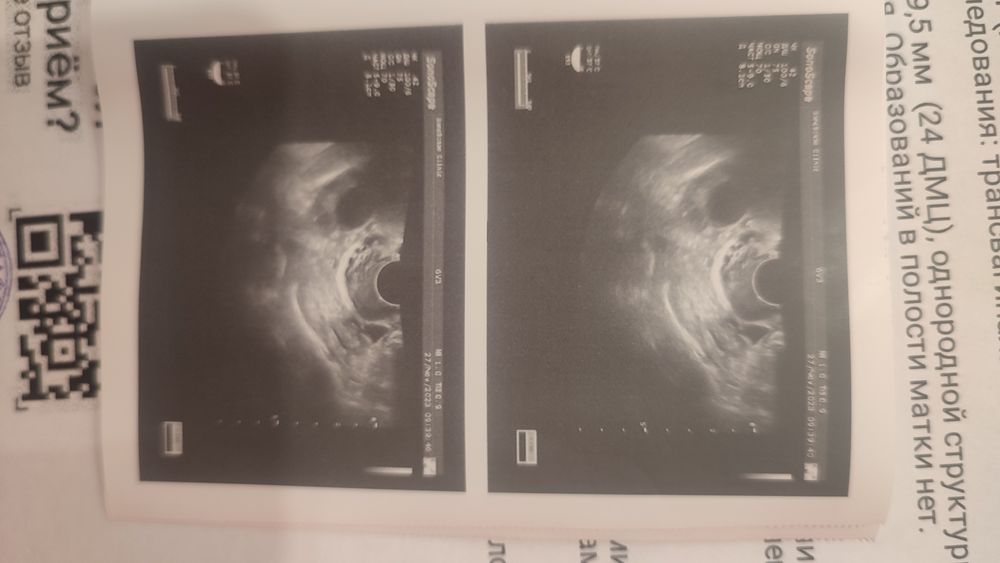

Девочки, я скоро сойду с ума. 4-9 октября прошли месячные, стимуляция кломиком по 50мг, снимки УЗИ от 22,24,27. УЗИ от 22ого показывает фолликул 20. Узи от 24ого у другого врача, где она говорит мне,что доминантный фолликул пошел уменьшаться 16 и овуляции в этом месяце не ждать. При этом на узи 27

ого есть фолликул 24 ,но есть и жидкость за шейкой (фото прикладываю), я не понимаю, у меня уже прошла овуляция,раз есть жидкость или что, но ведь нет жёлтого тела... Помогите пожалуйста разобраться 🙏